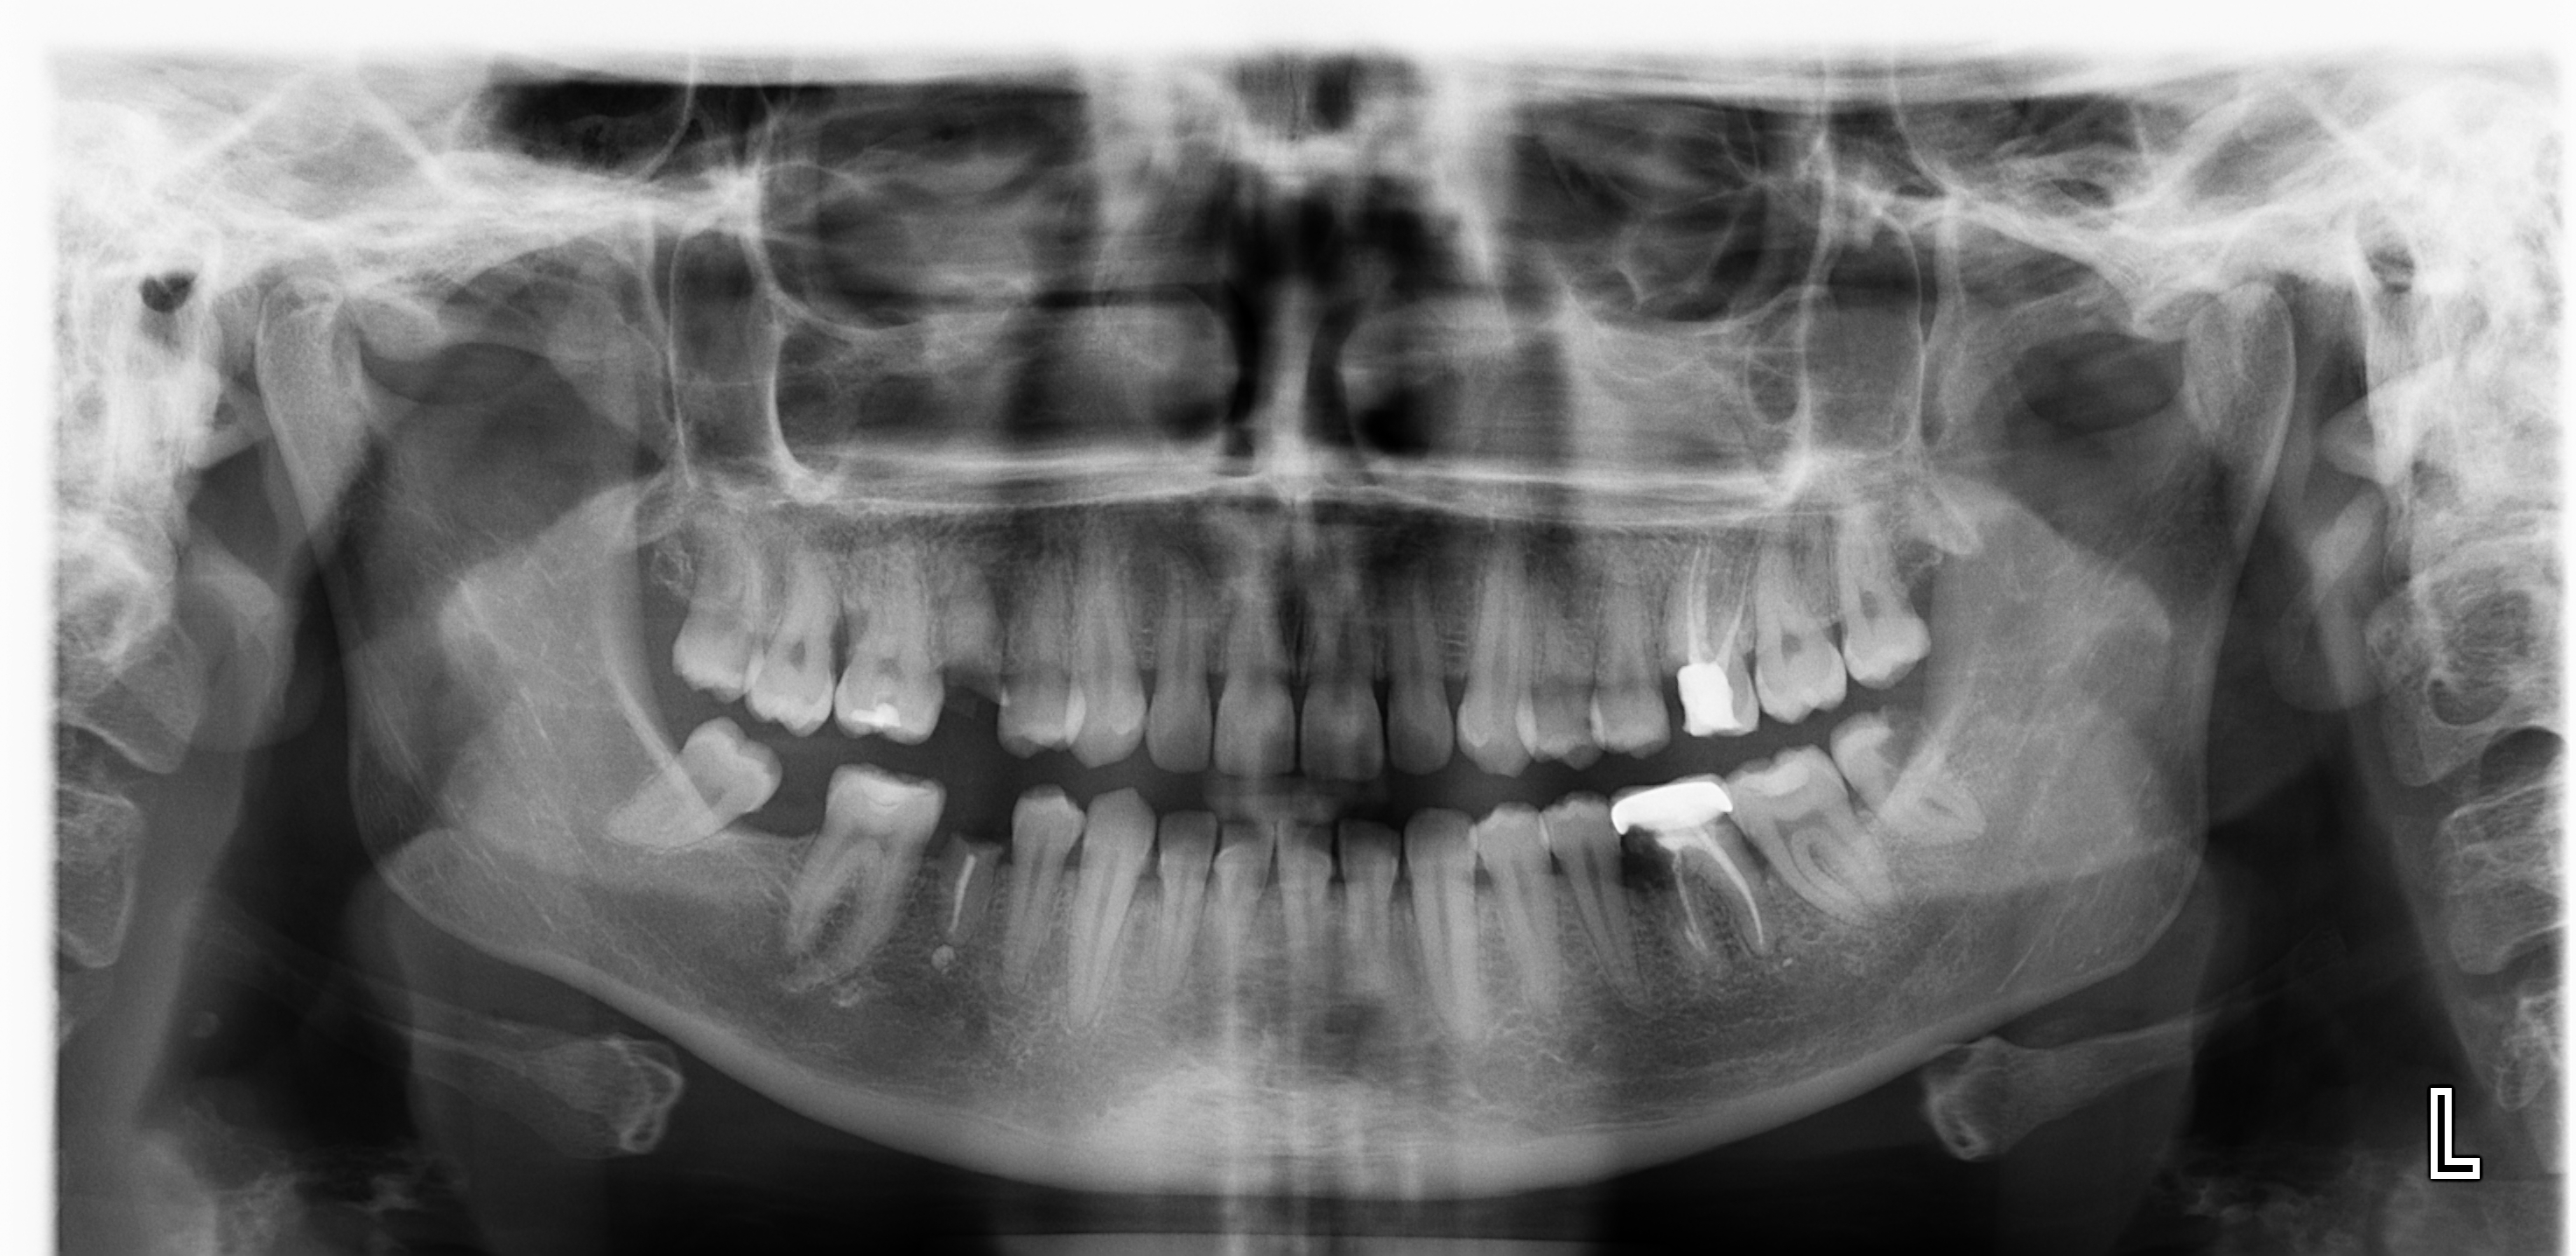

Pochissimi minuti e direttamente alla poltrona abbiamo già la Panoramica, senza richiedere esami all'esterno

Tecnologia CONE BEAN: è POSSIBILE ESEGUIRE UNA TAC IN POCHI MINUTI IN STUDIO.Con i nuovi apparecchi possiamo effettuare Tac dell'intera bocca o solo di una sua parte, sia per scopi diagnostici che per programmare terapie complesse come quelle implantari e chirugiche, con un dosaggio molto inferiore rispetto a quello di una TAC tradizionale.